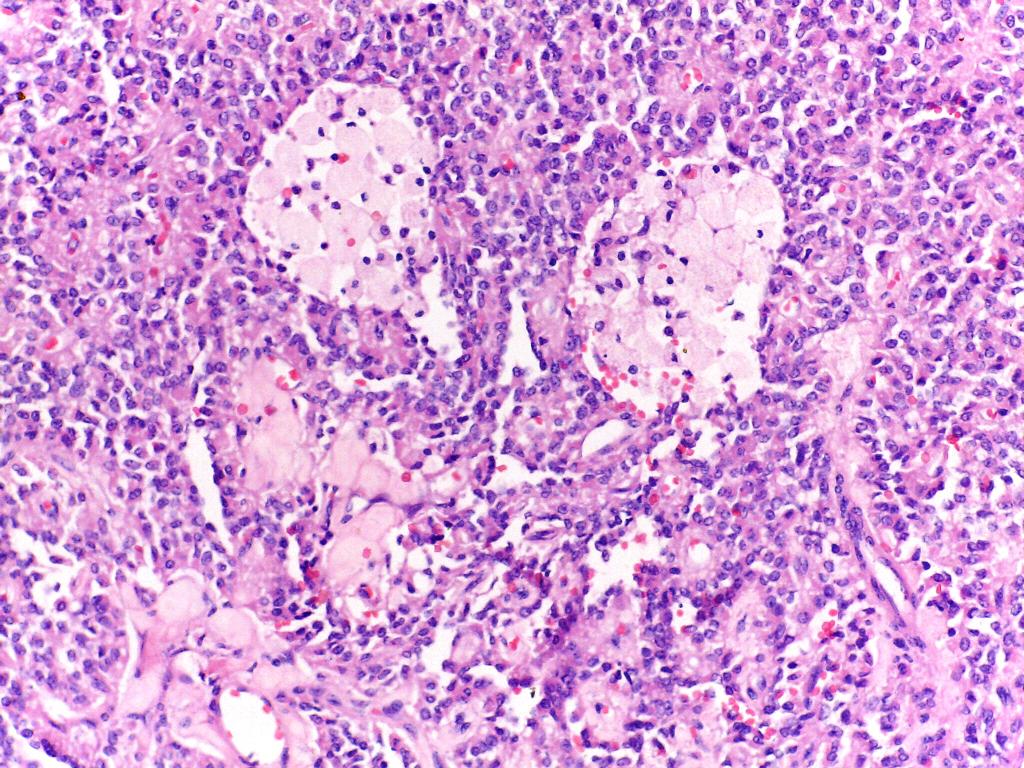

Caso del mes de Abril de 2020

Mujer de 25 años con tumor retroperitoneal

Respuesta:

Tumor sólido quístico papilar del pàncreas